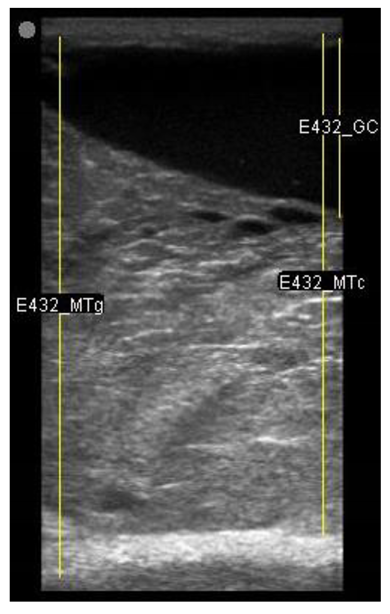

| 113 days of pregnancy (P113) Scanning depth 4.7 cm | ![]() | ![]() | MT generous: 28.9 mm MT conservative: 25.9 mm Gland cistern: 3.3 mm Parenchyma: 10.9 mm Fat Pad: 10.0 mm |